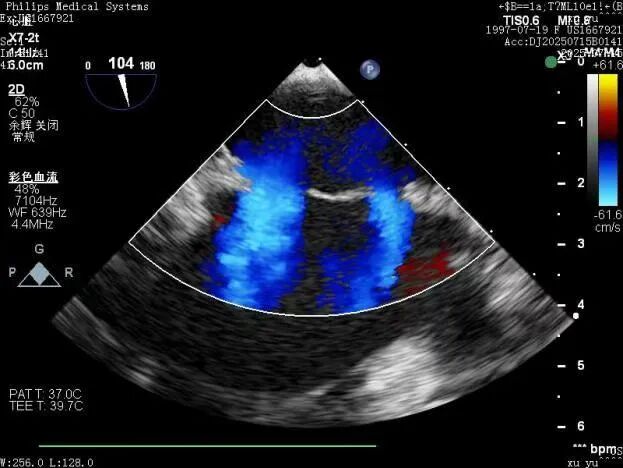

術前和術后TEE圖對比

手術過程中,憑借精湛技術和默契配合,團隊成功將兩枚可降解封堵器精準植入預定位置。術后即時超聲檢查顯示:兩處缺損封堵嚴密,無任何殘余分流,封堵器形態和位置理想,手術圓滿成功。術后,患者恢復良好,順利康復出院。